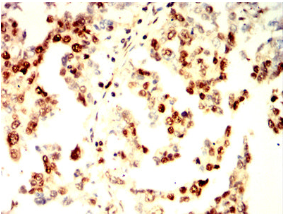

RAD23B Mouse Monoclonal antibody[6D2B3]

IHC    1/200 - 1/1000